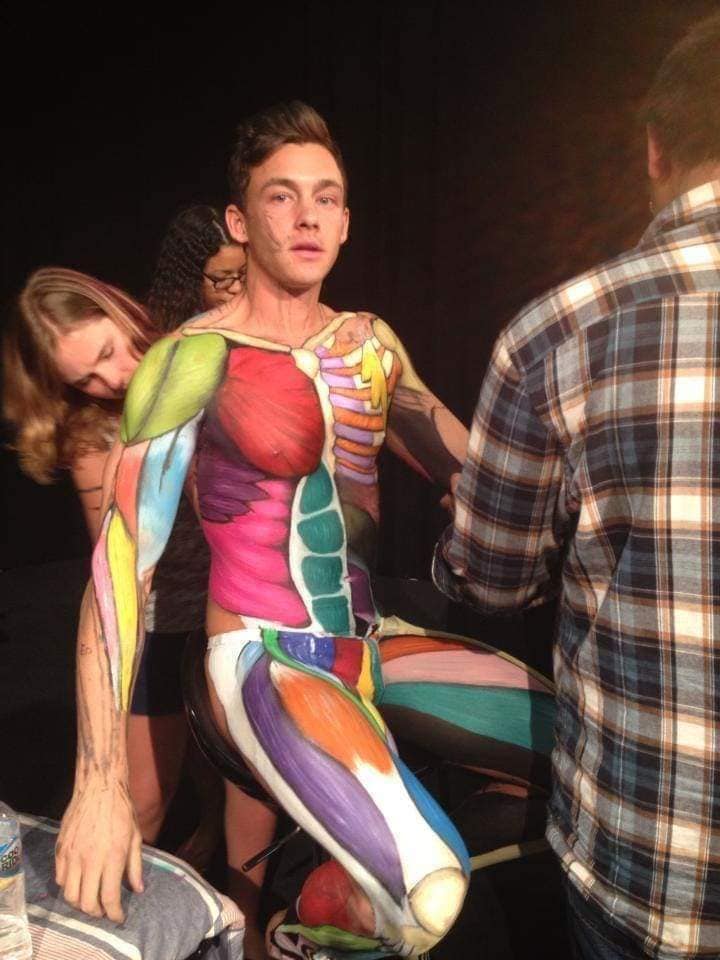

Скелетно-м'язова система людини (синоніми: Опорно-рухова система, опорно-руховий апарат, кістково-м'язова система, локомоторна система) — комплекс структур який утворює каркас, надає форму організму, дає йому опору та забезпечує захист внутрішніх органів і можливість пересування у просторі. Це функціональна сукупність кісток скелета, їх з'єднань (суглобів і сінартрозів), і соматичної мускулатури з допоміжними пристосуваннями, які здійснюють за допомогою нервової регуляції локомоції, підтримання пози, міміки та інших рухових діях, поряд з іншими системами органів утворює людське тіло.

Це саморушний механізм, який складається з 400 м'язів, 206 кісток і декількох сотень сухожиль. Більшість кісток скелету з'єднане рухомо за допомогою суглобів. Одним кінцем м'яз прикріплюється до однієї кістки, утворюючи суглоб, іншим кінцем — до іншої кістки. В англомовній літературі застосовують близькі за значенням терміни: англ. musculoskeletal system (скелетно-м'язова система) та англ. locomotor system (локомоторна система).

М'язова система людини є однією з основних систем організму, що відповідає за рухи, підтримання пози та стабільність. Вона складається з понад 600 м'язів, які можна класифікувати на скелетні, гладкі та серцеві м'язи. Скелетні м'язи, які є об'єктом нашого детального розгляду, дозволяють контролювати навколишній світ і виконувати різноманітні рухи. Особливу увагу в нашій статті буде приділено шейним і спинним м'язам, оскільки ці групи м'язів мають критичне значення для підтримання правильного постава та функціонування хребта.